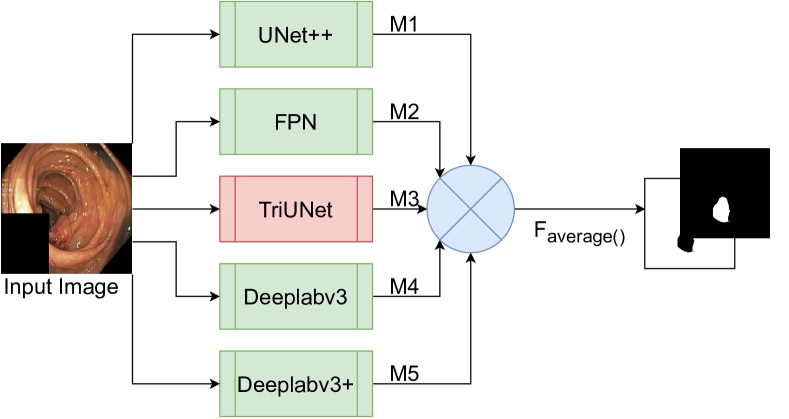

As shown in Figure 3, our configuration comprises five intermediate models, namely UNet++, FPN, DeepLabv3, DeepLabv3+, and TriUNet. The five intermediate models are first trained for number of epochs separately, where the best checkpoint of each model is selected to be combined in DivergentNet. This should be selected using a preliminary experiment. In our case, we identified that is enough to produce high-quality masks. However, training for more epochs may result in better checkpoints to use in DivergentNet. To produce the intermediate masks, the output of each model is passed through a softmax2d activation function. However, this should be changed based on the application. In our case, we predict masks for two classes, background and polyp, where no two categories may overlap. The masks produced by each intermediate model represent the divergent views on the data. The final output of DivergentNets is made by averaging the pixels between each intermediate mask and rounding to the nearest integer (either 0 or 1).